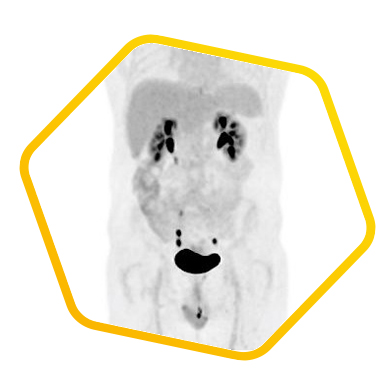

State-of-the-art technology in HKSH

Our Centre has acquired the first innovative digital SiPM PET/CT scanner in China to provide revolutionary breakthrough in PET imaging accuracy. This innovative technology precisely quantifies cell metabolism according to physiologic characteristics and molecular biochemical properties, which is applied to different clinical specialties such as oncology and neurology. Please click here for details.